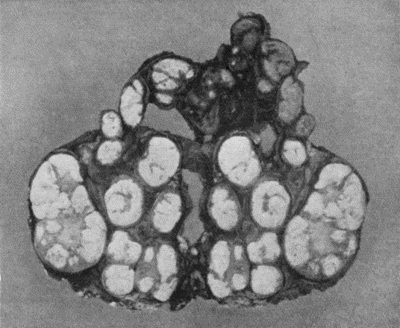

78.Mass of Tuberculous Glands removed from Axilla 333

79.Tuberculous Axillary Glands 335